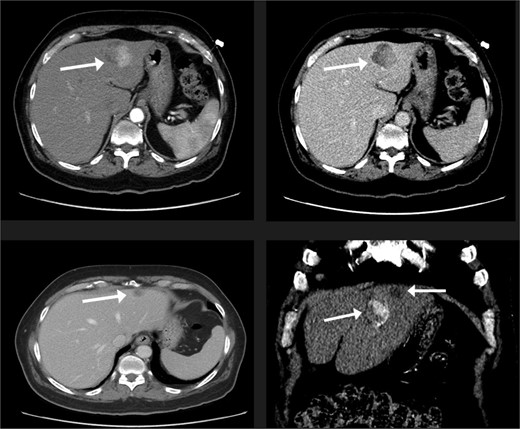

A 74-year-old man with right-handed colon cancer presented at the Emergency Department with a symptomatic anemia following chemotherapy and surgical intervention one year prior to the hepatocellular carcinoma resection. He reported 1-month history of paleness, dizziness, and exertional dyspnea, and fatiguability. Physical examination results were unremarkable. A chest CT angiography did not reveal a pulmonary embolism; however, two hepatic lesions, measuring 3.5 cm and 1.5 cm, in segment II were noted incidentally. Therefore, further laboratory tests were performed; hepatitis C virus was detected with a liver cirrhosis Child-Pugh score indicating class A disease; however, no tumor markers were detected. An abdominal CT revealed the two hepatic lesions in segment II, the larger lesion (3.8 cm × 3.4 cm) demonstrated arterial enhancement and faint washout in the delayed phase (Fig. 1). The smaller lesion measured 1.2 cm × 1.1 cm (Fig. 1). An abdominal MRI was performed to characterize the hepatic lesions: one lesion was consistent with HCC and the second was metastatic from mucinous which was visible previously on imaging at the time of diagnosis of colon cancer (Fig. 2). Furthermore, the biopsy of the two liver lesions confirmed the diagnoses of HCC and metastatic colon cancer. Subsequently, the case was discussed within a multidisciplinary tumor board (MDTB), where the decision was made to perform chemotherapy and trans arterial chemoembolization for the HCC lesion. Upon follow-up evaluation, segment II hepatic lesion size had decreased to 1.6 × 2.4 cm (previously was 3.8 × 3.4 cm) and 1.5 × 1.3 cm (previously 1.2 × 1.1 cm). Consequently, the case was rediscussed in MDTB, and it was decided to proceed with liver resection of the two lesions. Following this, the patient underwent left lateral lobectomy, common hepatic artery dissection, porta hepatis lymph node dissection, and cholecystectomy. Postoperative pathology showed a residual 2.3-cm-sized differentiated HCC and a metastatic colonic-type adenocarcinoma with a mucinous differentiation which was 1.2 cm in size. The two lesions measured 0.7 cm apart (Fig. 3). All lymph nodes dissected from the porta hepatis, and the common hepatic artery were positive for metastatic colonic type adenocarcinoma. The patient’s postoperative course was unremarkable, and he was discharged 12 days later. Following a discussion within the MDTB, it was decided to continue adjuvant chemotherapy.

Two segment II hepatic lesions: the larger lesion is consistent with clear cell variant hepatocellular carcinoma and the second, more cranial lesion, is likely metastasis from a mucinous adenocarcinoma.